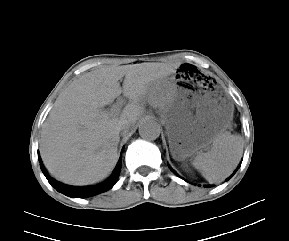

标题: CT19533:病变来源于哪?

患者,男,发现上腹部包块两月余。

病变位于肝胃间隙,实际就是位于小网膜囊(左肝下后间隙),呈轻度不均匀性强化,腹腔内及腹膜后见多发肿大淋巴结。所以我考虑肝胃间隙恶性胃肠间质瘤并淋巴结转移。

病灶强化不显著,灶周及腹膜后见多量淋巴结肿大,考虑淋巴瘤可能,其次考虑间质瘤

病灶与胰腺分界不清,来源于胰腺?

强化后病变与胃壁分界清楚,并且血供不是来源胃壁血管。考虑胰腺颈体癌并腹腔腹膜后淋巴结转移。

考虑胃肠间质瘤,病灶与胰腺分界不清,不除外胰腺肿瘤!